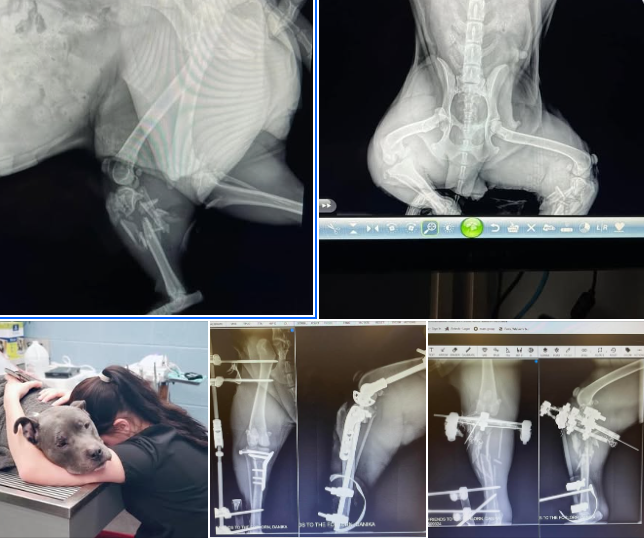

We donated to Army's Legacly Animal and Rescue Sanctuary, Inc. For the care of this poor pup was found at the Residence Inn on Dunfey Ln 04/2025

We donated Friends to the Forlorn -This surgery and her hospitalization will come to over $10,000.00 we have raised $4300.00 of it so far .. we need $5700.00 to cover her medical expenses 04/2022

BARC CT - Emergency surgery for issues involving bladder stones, it's complicated and costly 04/22